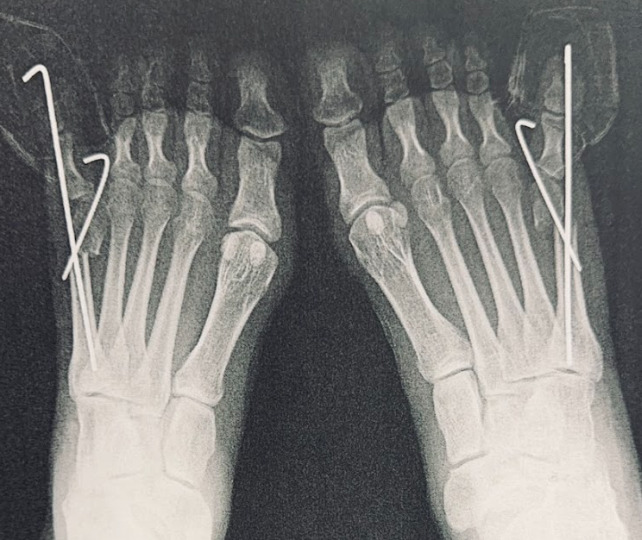

内反小趾の手術療法

手術療法は外反母趾と同様に、中足骨の近位で行う骨切り術、骨幹部で行う骨切り術、遠位で行う骨切り術に分類されます。第5中足骨の近位骨切り術としては、矯正力が大きいものの骨癒合が不安視されるdome-shaped osteotomyが報告されています。遠位骨切り術としては、distal chevron osteotomyやpercutaneous distal osteotomy、distal oblique osteotomy、逆Mitchell法などが報告されています。しかし、遠位骨切り術では第5中足趾節間(MTP)関節の可動域制限や第5中足骨頭の壊死が懸念されます。骨幹部骨切り術としては、longitudinal diaphyseal osteotomyやScarf法が報告されており、良好な術後成績を収めています。